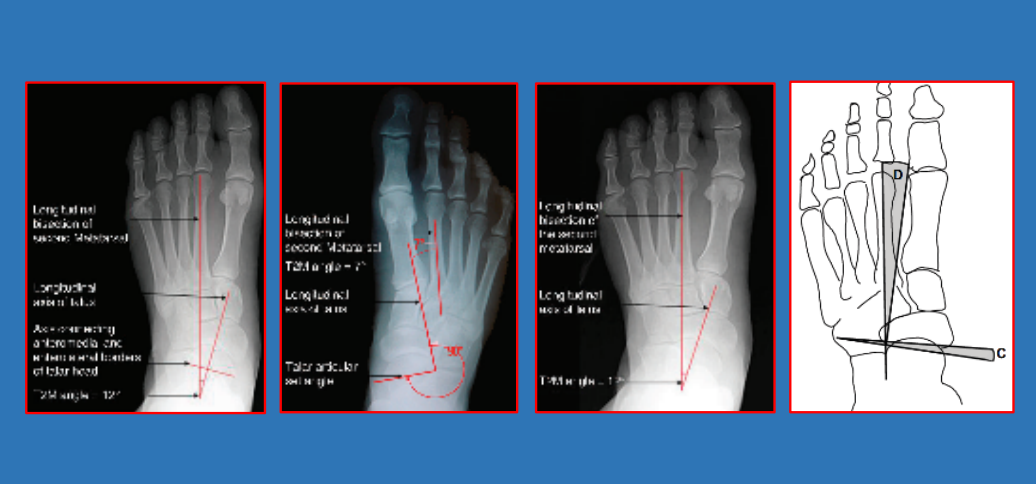

20 前后足—正位距骨第一/第二跖骨角

21 前足—拇外翻

拇外翻角Hallux valgus angle,HVA(metatarsophalangeal angle,MTP-1)

正常 < 15°

轻度 < 20°

中度 20°~40°

重度 > 40°

第一、二跖骨间角Intermetatarsalangle,IM 1-2

正常 < 9°

轻度 9°~11°

中度 11°~16°

重度 > 16°

跖骨远端关节角(DMAA)正常<8°